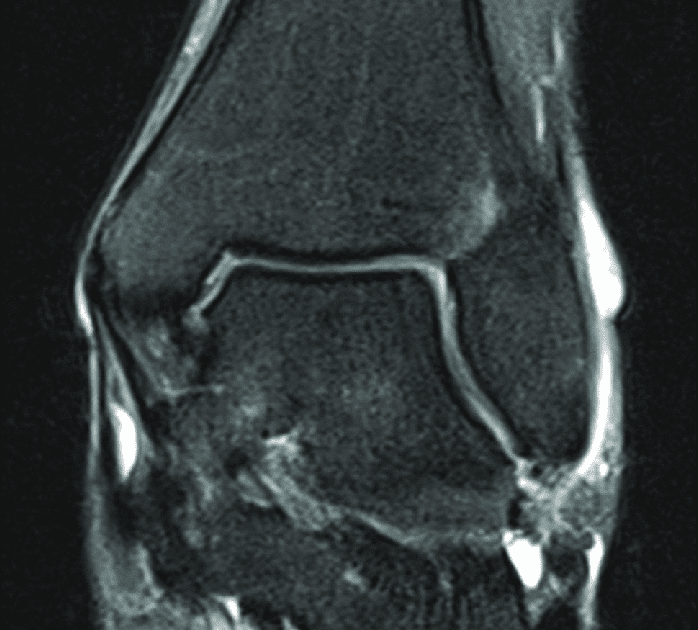

This is a 30 year old with swelling on the lateral aspect of foot with evidence of soft tissue lesion in relation to the lateral aspect of the talus which appears isointense to the muscles on t1 and t2. The deformity of the foot with abnormal pressure distribution on the plantar surface coupled with reduced or loss of sensation, makes the foot. Learn about foot and ankle mri here. If you'd like to support us and get something great in return. Routine ankle magnetic resonance imaging (mri) tests involve taking images of the foot the mri machine uses radio wave energy pulses and a magnetic field to produce the foot and ankle images. Gray's anatomy for students, 2nd ed. Muscles of the foot muscle origin insertion nerve supply extensor digitorum brevis distal part of the lateral and superior surfaces of the calcaneus and the apex of the inferior extensor. Intrinsic foot muscles differ from extrinsic foot muscles, which have their origins in the leg and the long tendons cross the ankle joint complex 27. Explore more like foot muscle anatomy mri. Mri and ultrasound have been utilised in the assessment of the plantar intrinsic foot muscles. Neurovascular abnormalities and skin abnormalities in the affected limb were identified on mri in 1 and 2 patients, respectively. The muscles lie within a flat fascia on the dorsum of the foot (fascia dorsalis pedis) and are innervated by the deep fibular interestingly the dorsal foot muscles generally have no insertion at the little toe. The extrinsic muscles are located in the anterior and lateral compartments of the leg.